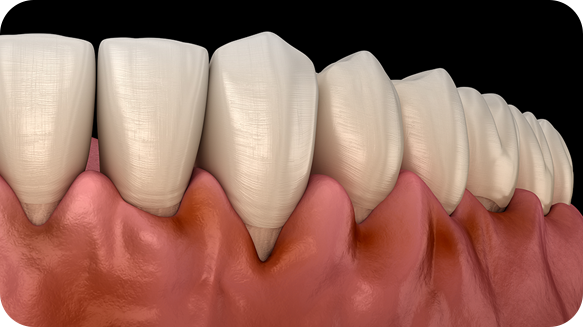

붓고 피나는 잇몸을 건강하게 잇몸치료로 회복하세요!

건강한 치아는 건강한 잇몸이 있기에 존재합니다. 성인의 절반 이상이 잇몸 질환을 모르고 방치하고 있습니다. 잇몸질환, 꾸준한 관리를 통해 개선해드리겠습니다.

잇몸 질환 치료에는 비수술적 치료와 수술적 치료 방법이 있습니다.

건강한 잇몸

치주낭 길이 3mm 이하

스케일링 치료

치은염

치주낭 길이 3~5mm 이하

치근활택술 치료

초기 치주염

치주낭 길이 5~7mm 이하

치주소파술 치료

중기 치주염

치주낭 길이 7mm 이상

치주 수술